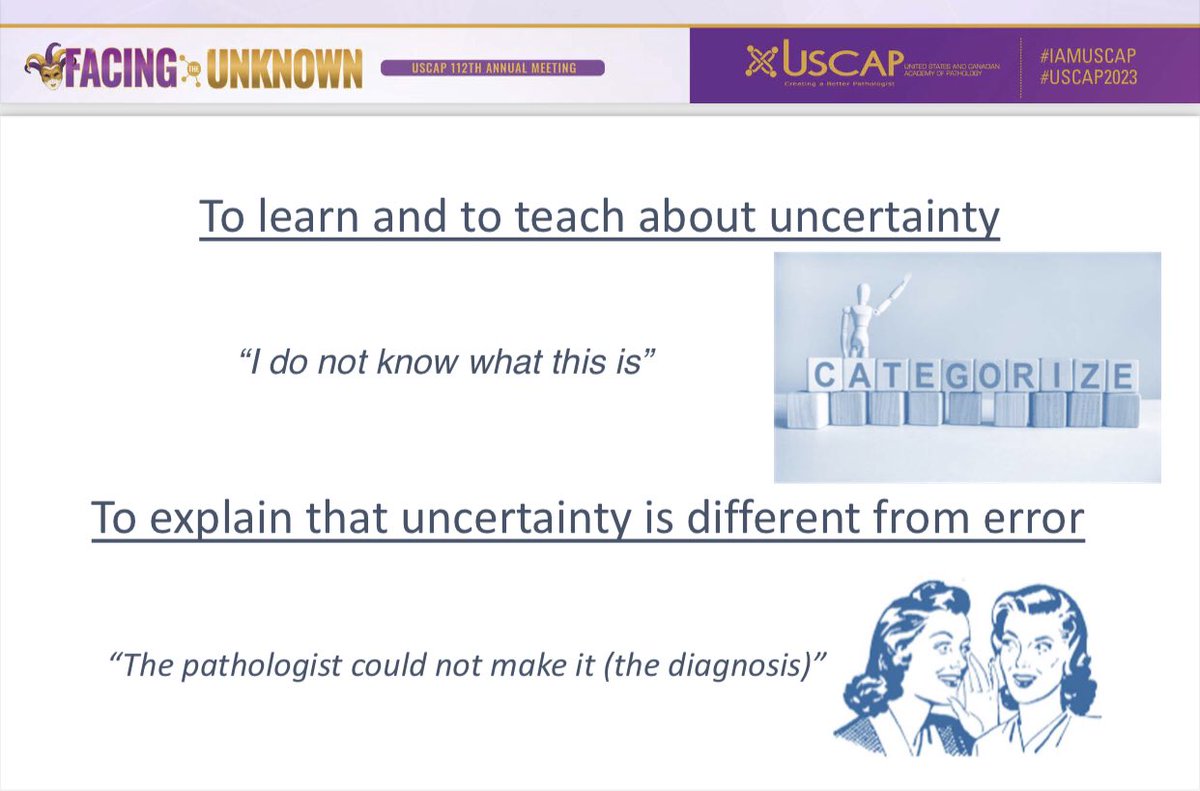

Very good conference in the European Society of Pathology (ESP) Meeting at #USCAP2023 by Catarina Eloy, MD,PhD It was pleasure see you again ☺️ Pic with Héctor-Enrique Torres-Rivas, MD an expert in Cytology and interventional cytology 💉

Today at #USCAP2023 the European Society of Pathology (ESP) companion meeting took place! We would like to thank the moderators, speakers and most of all the attendees for an exciting meeting with lively discussions! #PathTwitter